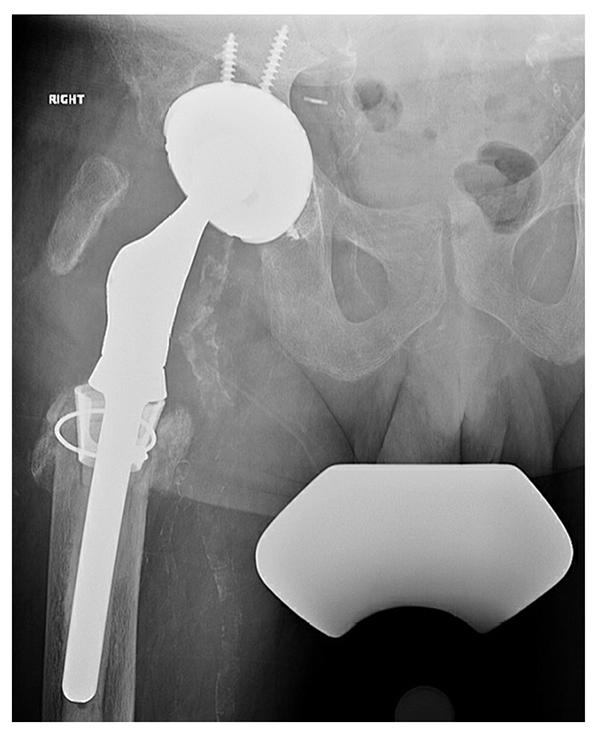

A trial with a proximal femoral replacement (Stryker GMRS) revealed that the largest size, 18 mm, was still significantly smaller than the diameter of the diaphysis. Therefore, we used a construct more common in distal femoral replacement, the Stryker tibial cone system, with gentle hand preparation of the diaphyseal orifice. With the cone trial in place, the proximal femoral trial had better axial and rotational stability. We placed a size-C Stryker cone that was impacted in place, as well as a proximal femoral stem (size 15 × 127 mm) fixed with vacuum mixed cement containing gentamicin and vancomycin (Fig. 4). A dual mobility liner was placed to minimize the risk of instability. The intraoperative cultures were negative and postoperatively the patient had a similar restriction and weight bearing of only 20% for 3 months. He then began weight bearing with a cane, with minimal pain and no apparent leg length discrepancy.

Figure 4: Most recent radiograph shows a highly porous revision acetabular component and cemented proximal femoral replacement with a diaphyseal engaging tibial cone.